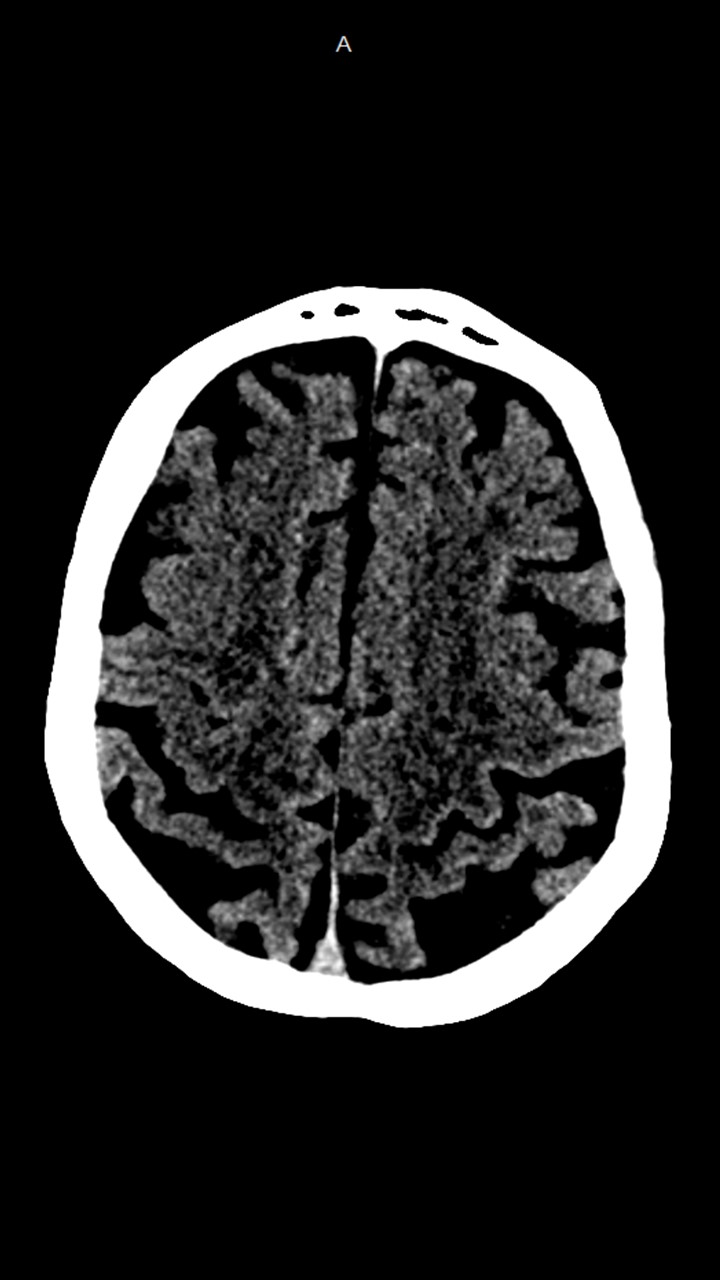

Hallazgos de TC de craneo:

• Cambios de leucoaraiosis periventricular.

• Hay zonas de hipodensidad subcortical fronto-parietal superior predominantemente izquierdas, de aspecto inespecíficos.

• Los halazgos son inespecificos, ante la ausencia de patología hemorragica aguda se decide continuar con el protocolo habitual.